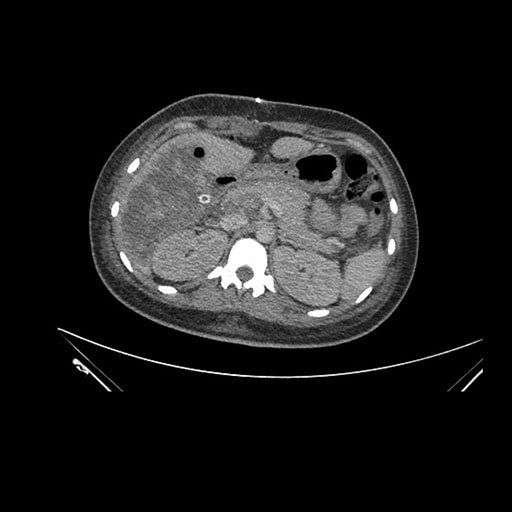

Axial Arterial

Axial Venous

Imaging analysis

Based on initial findings, which issue(s) would you be most concerned about?